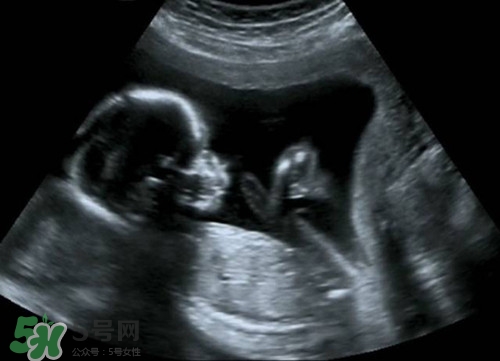

懷孕之后b超肯定是要做的,那么懷孕多久后可以做b超呢?做b超的話會(huì)影響到孩子嗎?下面我們來一起介紹下吧!

--懷孕40天后就可以做B超檢查的了

意見建議:孕期一般做3-5次B超,孕早期一次,目的是為了確定妊娠,估計(jì)胚胎發(fā)育,診斷孕早期常見疾病如宮外孕,葡萄胎,各種類型的流產(chǎn).孕中期也就是孕22-26周做四維彩超排畸篩查看看胎兒有無(wú)大體畸形及主要臟器畸形.孕晚期看胎兒,羊水及胎盤情況.

孕期做B超檢查是很有必要的.但是孕期做B超不要超過3次.一般是懷孕早期應(yīng)通過B超確定宮內(nèi)的妊娠是否正常.一般提倡于懷孕早期通過做B超明確是否是宮內(nèi)正常妊娠或雙胎,葡萄胎等.懷孕中期,大約在閉經(jīng)16周左右需要再做一次B超,以確定胎兒有無(wú)畸形和生長(zhǎng)發(fā)育是否正常.因?yàn)槿绻@時(shí)發(fā)現(xiàn)胎兒不正常,在閉經(jīng)20周以內(nèi)中止妊娠,是比較適宜的.懷孕晚期,即閉經(jīng)36周以后,做B超可以明確羊水多少以及胎盤的功能.羊水過多或過少,以及胎盤鈣化或功能不良,都不應(yīng)再繼續(xù)妊娠.必要時(shí)需進(jìn)行剖腹產(chǎn)

目前臨床上所應(yīng)用的B超,其探頭發(fā)射的聲強(qiáng)度小于10毫瓦/平方厘米,而且超聲檢查的時(shí)間往往只有5~10分鐘,對(duì)每個(gè)器官的探測(cè)時(shí)間更短.所以說,B超檢查對(duì)胎兒的危害是極小的,不會(huì)影響胎兒的身心發(fā)育.因此,孕婦不必對(duì)孕期B超檢查產(chǎn)生恐懼心理,適時(shí)的B超檢查是確保胎兒正常發(fā)育的重要手段.

正常情況下,妊娠早期應(yīng)進(jìn)行一次B超檢查,以明確是否妊娠,并確定妊娠的天數(shù).